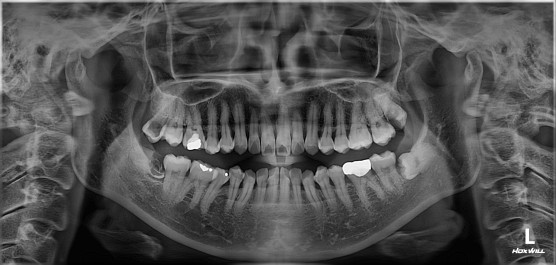

사랑니#48 사랑니 발치

치료 기간  2024. 03. 12 당일 치료

cc. #48 발치 원하심

K01.173 하악 제3대구치 의 매복